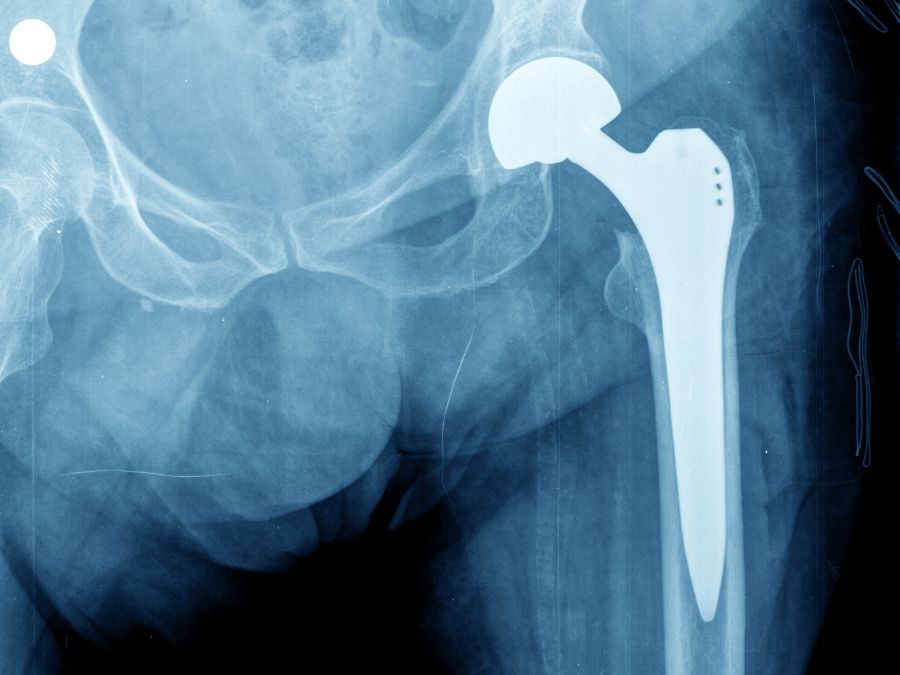

News La scelta della protesi: come fa il chirurgo a scegliere la migliore per il paziente Leggi » 6 Giugno 2025